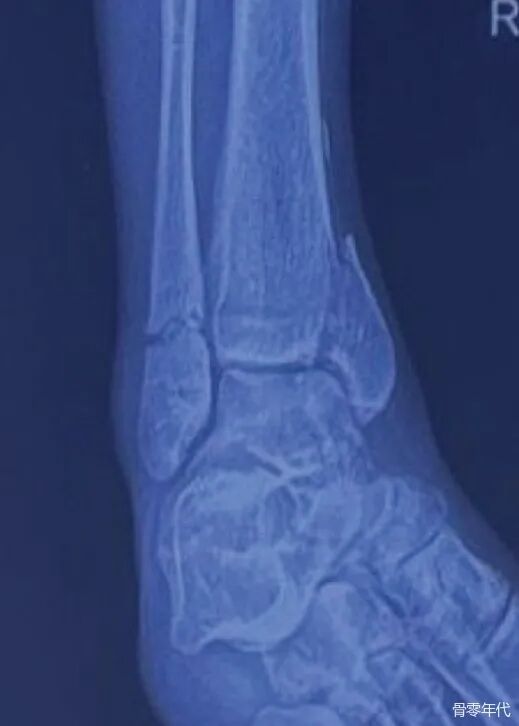

影像学表现